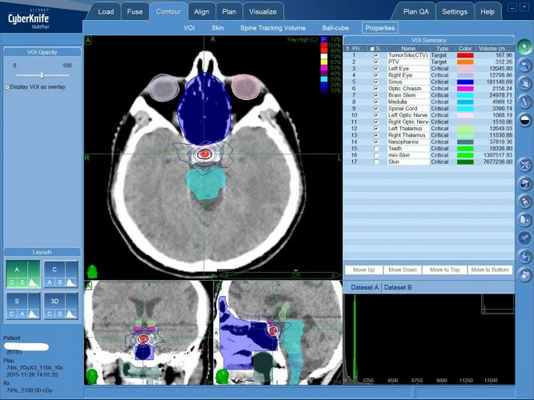

- стереотаксическая радиохирургия (роботизированный комплекс КиберНож);

При радиохирургии сама аденома гипофиза разрушается бесконтактным способом. КиберНож с высочайшей точностью дистанционно подает в определенный при предварительной диагностике объем опухоли в мозге множественные тонкие пучки излучения. Из пучков формируется зона высокой дозы ионизирующего излучения, соответствующая форме опухоли в мозге пациента.

При таком лечении высокая доза излучения концентрируется точно в объеме опухоли, что приводит к разрушению клеток аденомы гипофиза. При этом здоровые ткани головного мозга, окружающие гипофиз, получают крайне низкую дозу.

План лечения аденомы гипофиза на КиберНоже. Небольшая красная зона в центре головного мозга, показанного в трех проекциях — это та зона, в которой будет сформирована зона высокой дозы ионизирующего излучения.

План лечения рассчитывается мощнейшим программным комплексом и заверяется медицинским физиком, лучевым терапевтом и лечащим врачом.